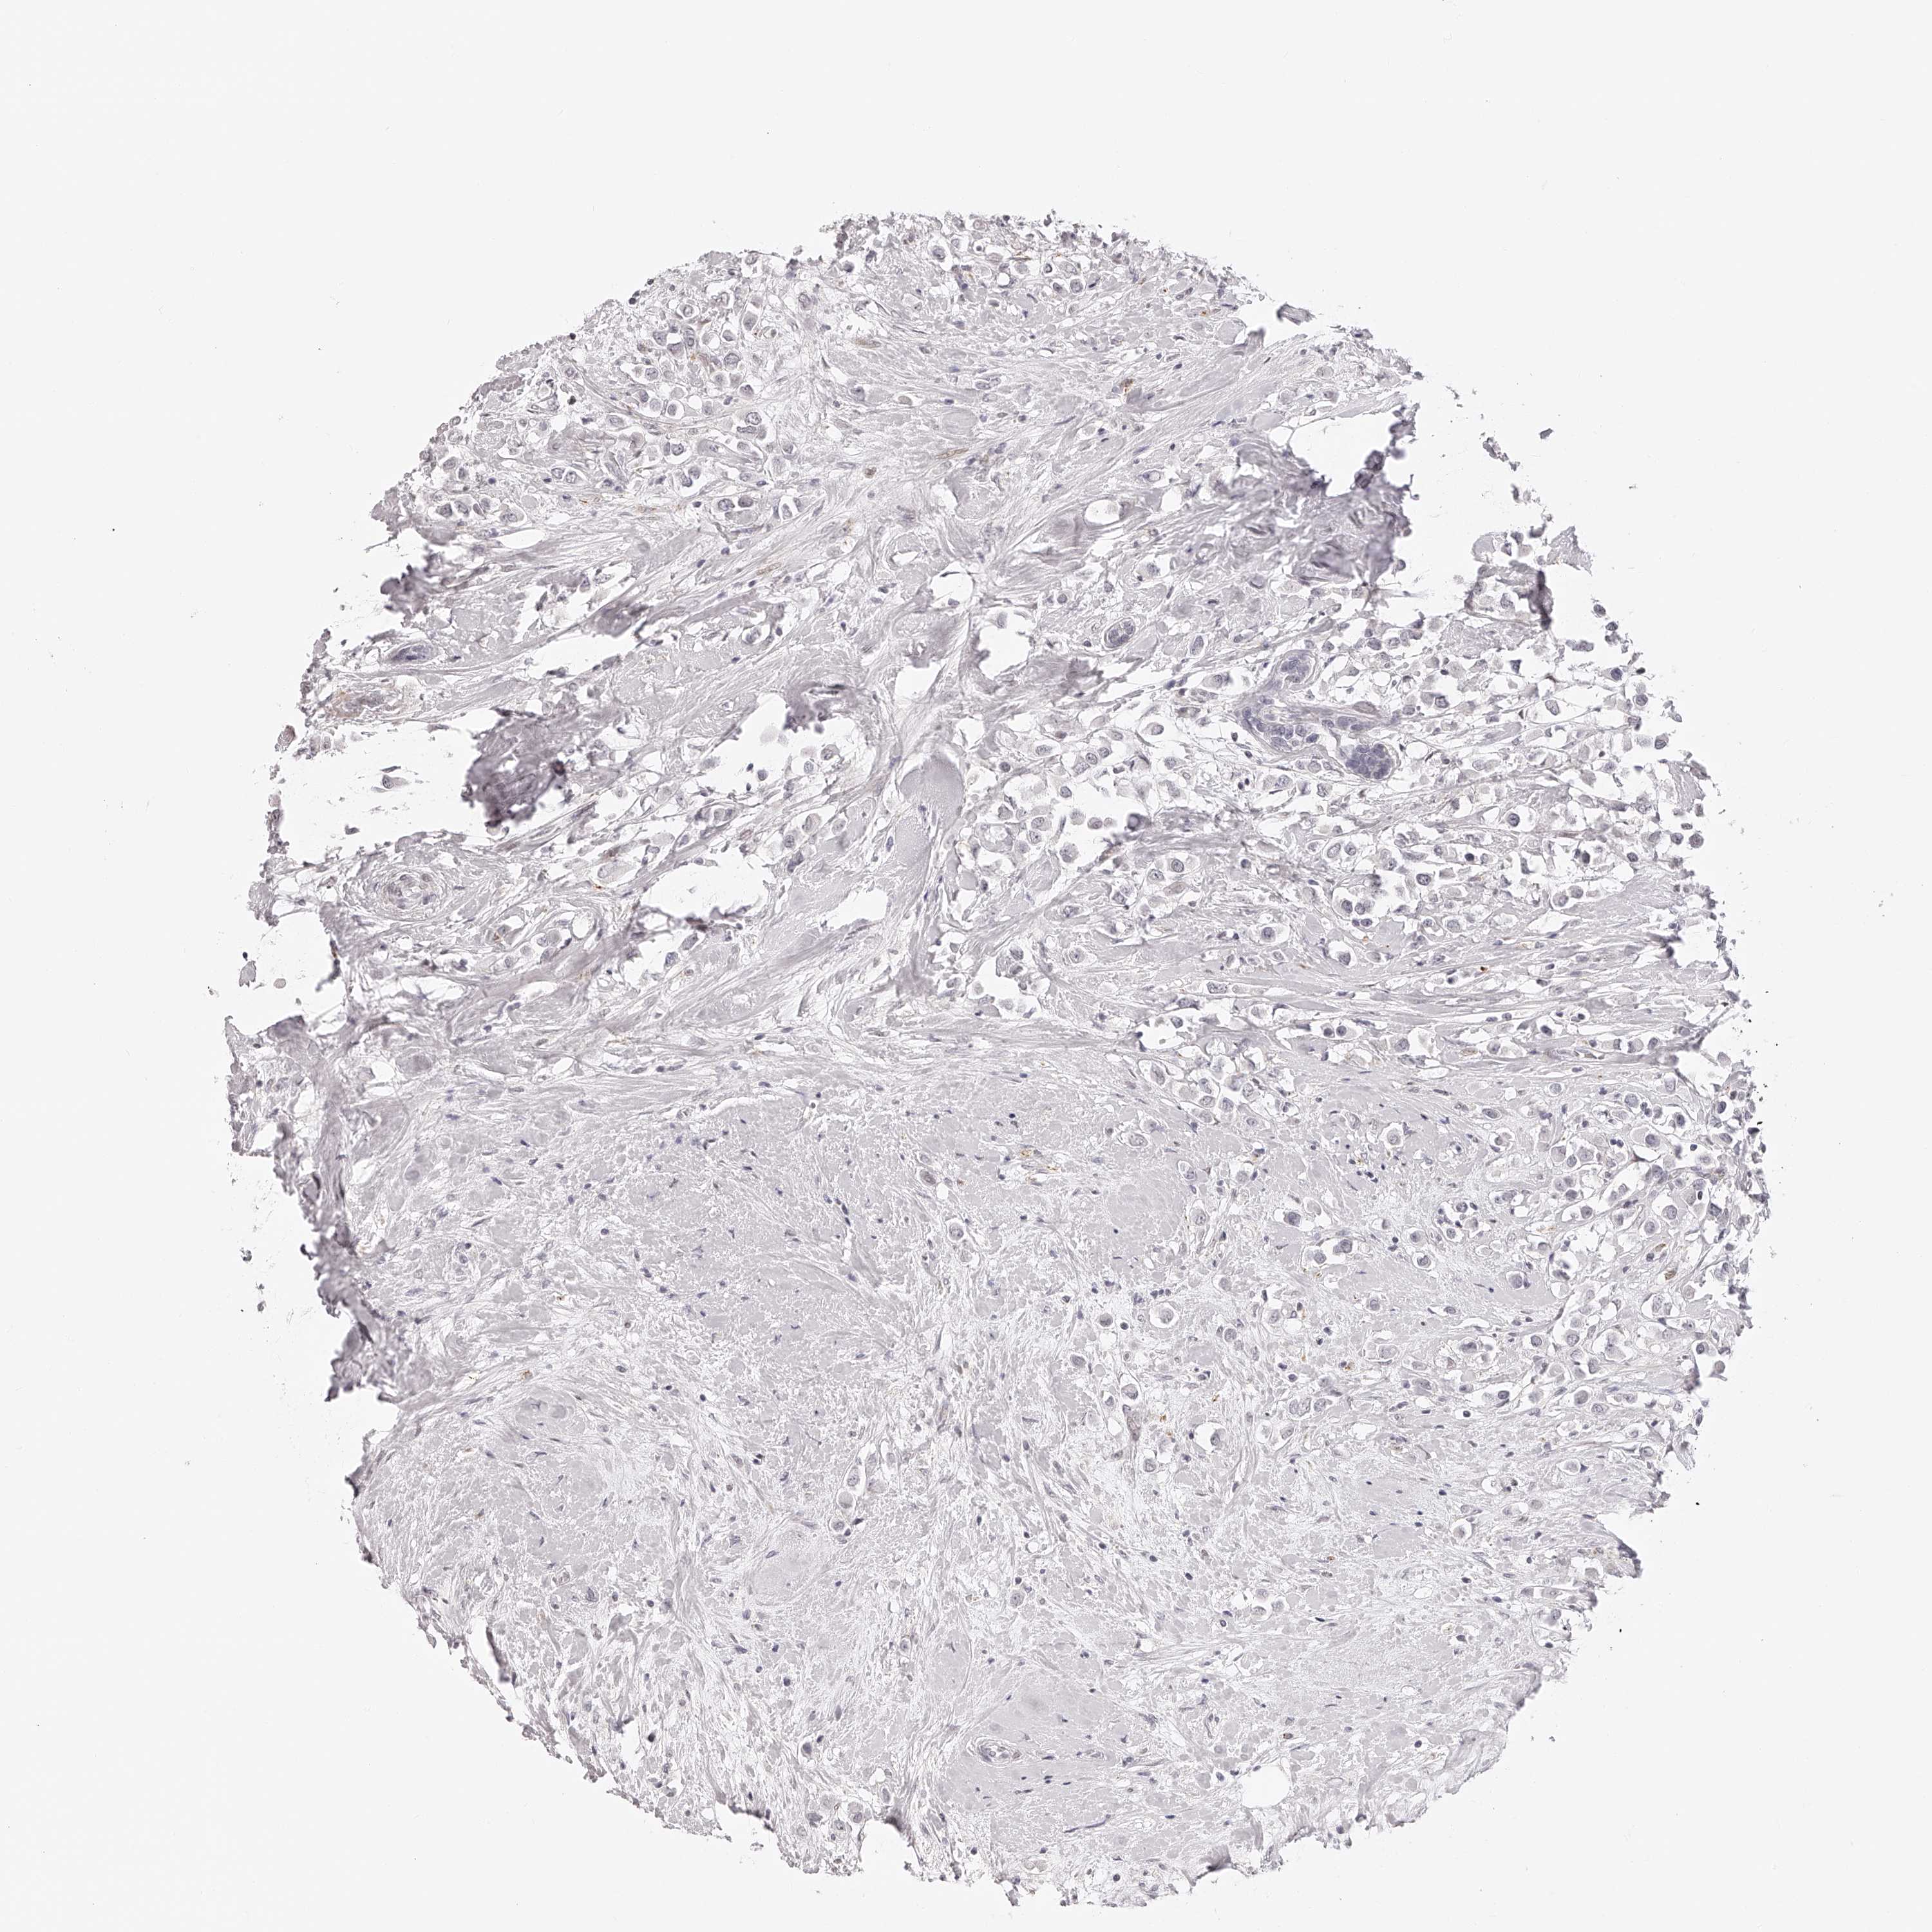

CANCER BREAST CANCER Show tissue menu

BRCA TCGA BRCA VALIDATION PROTEIN EXPRESSION